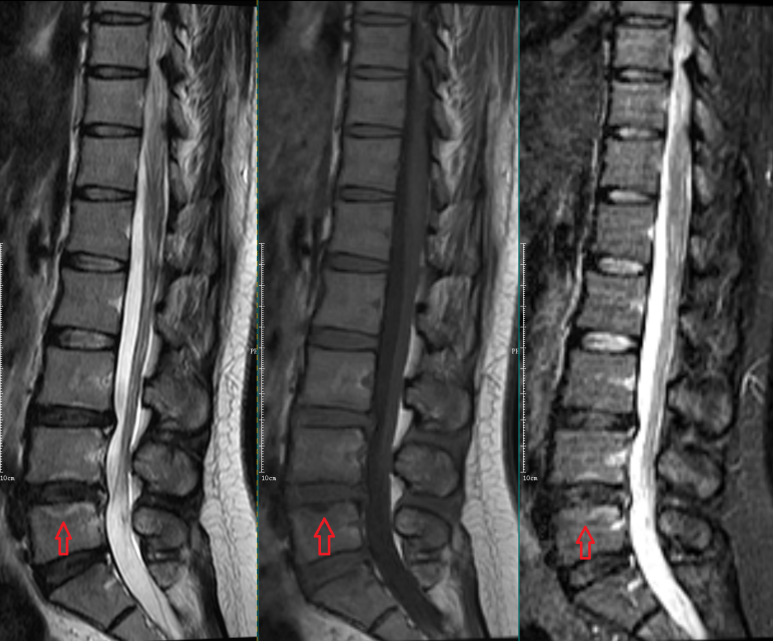

Modic Ⅱ型:

L4-5椎间盘上下缘见条带状异常信号,T1WI高信号,T2WI高信号,STIR序列低信号。

L5-S1椎间盘上下缘见条带状异常信号,T1WI高信号,T2WI高信号,STIR序列低信号。